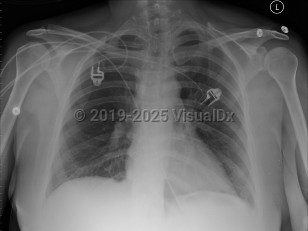

Pulmonary edema

Acute respiratory distress syndromeAcute respiratory distress syndrome